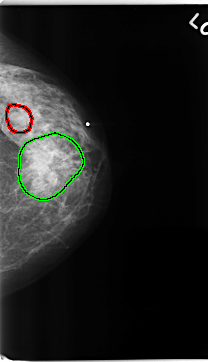

FILE: C_0229_1.LEFT_CC.OVERLAY

TOTAL_ABNORMALITIES 2

ABNORMALITY 1

LESION_TYPE MASS SHAPE OVAL MARGINS CIRCUMSCRIBED

ASSESSMENT 3

SUBTLETY 5

PATHOLOGY BENIGN

TOTAL_OUTLINES 1

BOUNDARY

ABNORMALITY 2

LESION_TYPE MASS SHAPE IRREGULAR MARGINS SPICULATED

ASSESSMENT 5

PATHOLOGY MALIGNANT